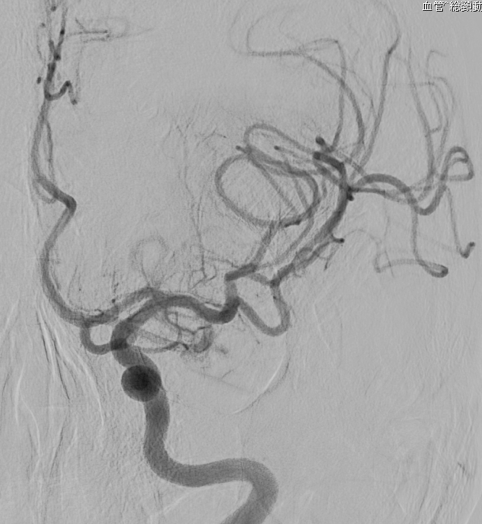

Apoplexy 21

【術前】

Apoplexy 22

【フローダイバーダー留置】

Apoplexy 23

【半年後】

フローダイバーター治療の放射線学的画像